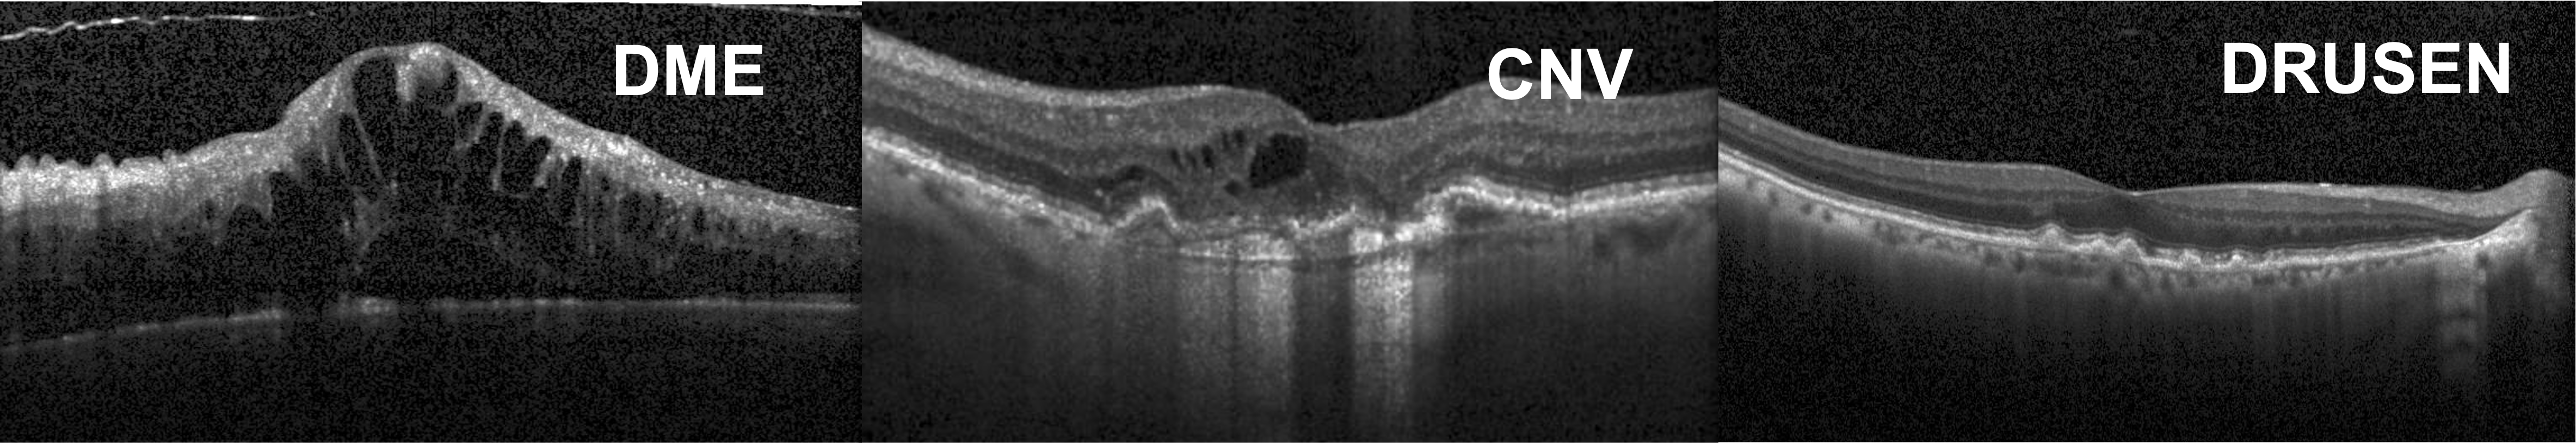

The dataset used in this paper, obtained from [6], has grayscale, cross-sectional, foveal OCT scans of varying sizes belonging to an unbalanced distribution of a healthy class and three types of retinal diseases: Drusen, choroidal neovascularization (CNV) and diabetic macular edema (DME). We are interested in distinguishing between the disease states and thus use only imagery from these three classes for fine-grained classification. Sample imagery from each class is shown in Fig. 4. A total of 10488 DME, 36345 CNV and 7756 Drusen images from 1852 patients were used in the training and unlabeled set. Within the test set, there were 250 images for each disease collected from 486 patients. All imagery were resized to 128×128128128128\times 128 and normalized to have zero mean and unit standard deviation. Additional implementation details are shown in Table 1. There was no overlap in patients or imagery in train or test sets. The patient and class distribution in train and test sets are shown in Fig. 5.

Refer to caption

Fig. 4: Cross-sectional OCT of the three retinal diseases.